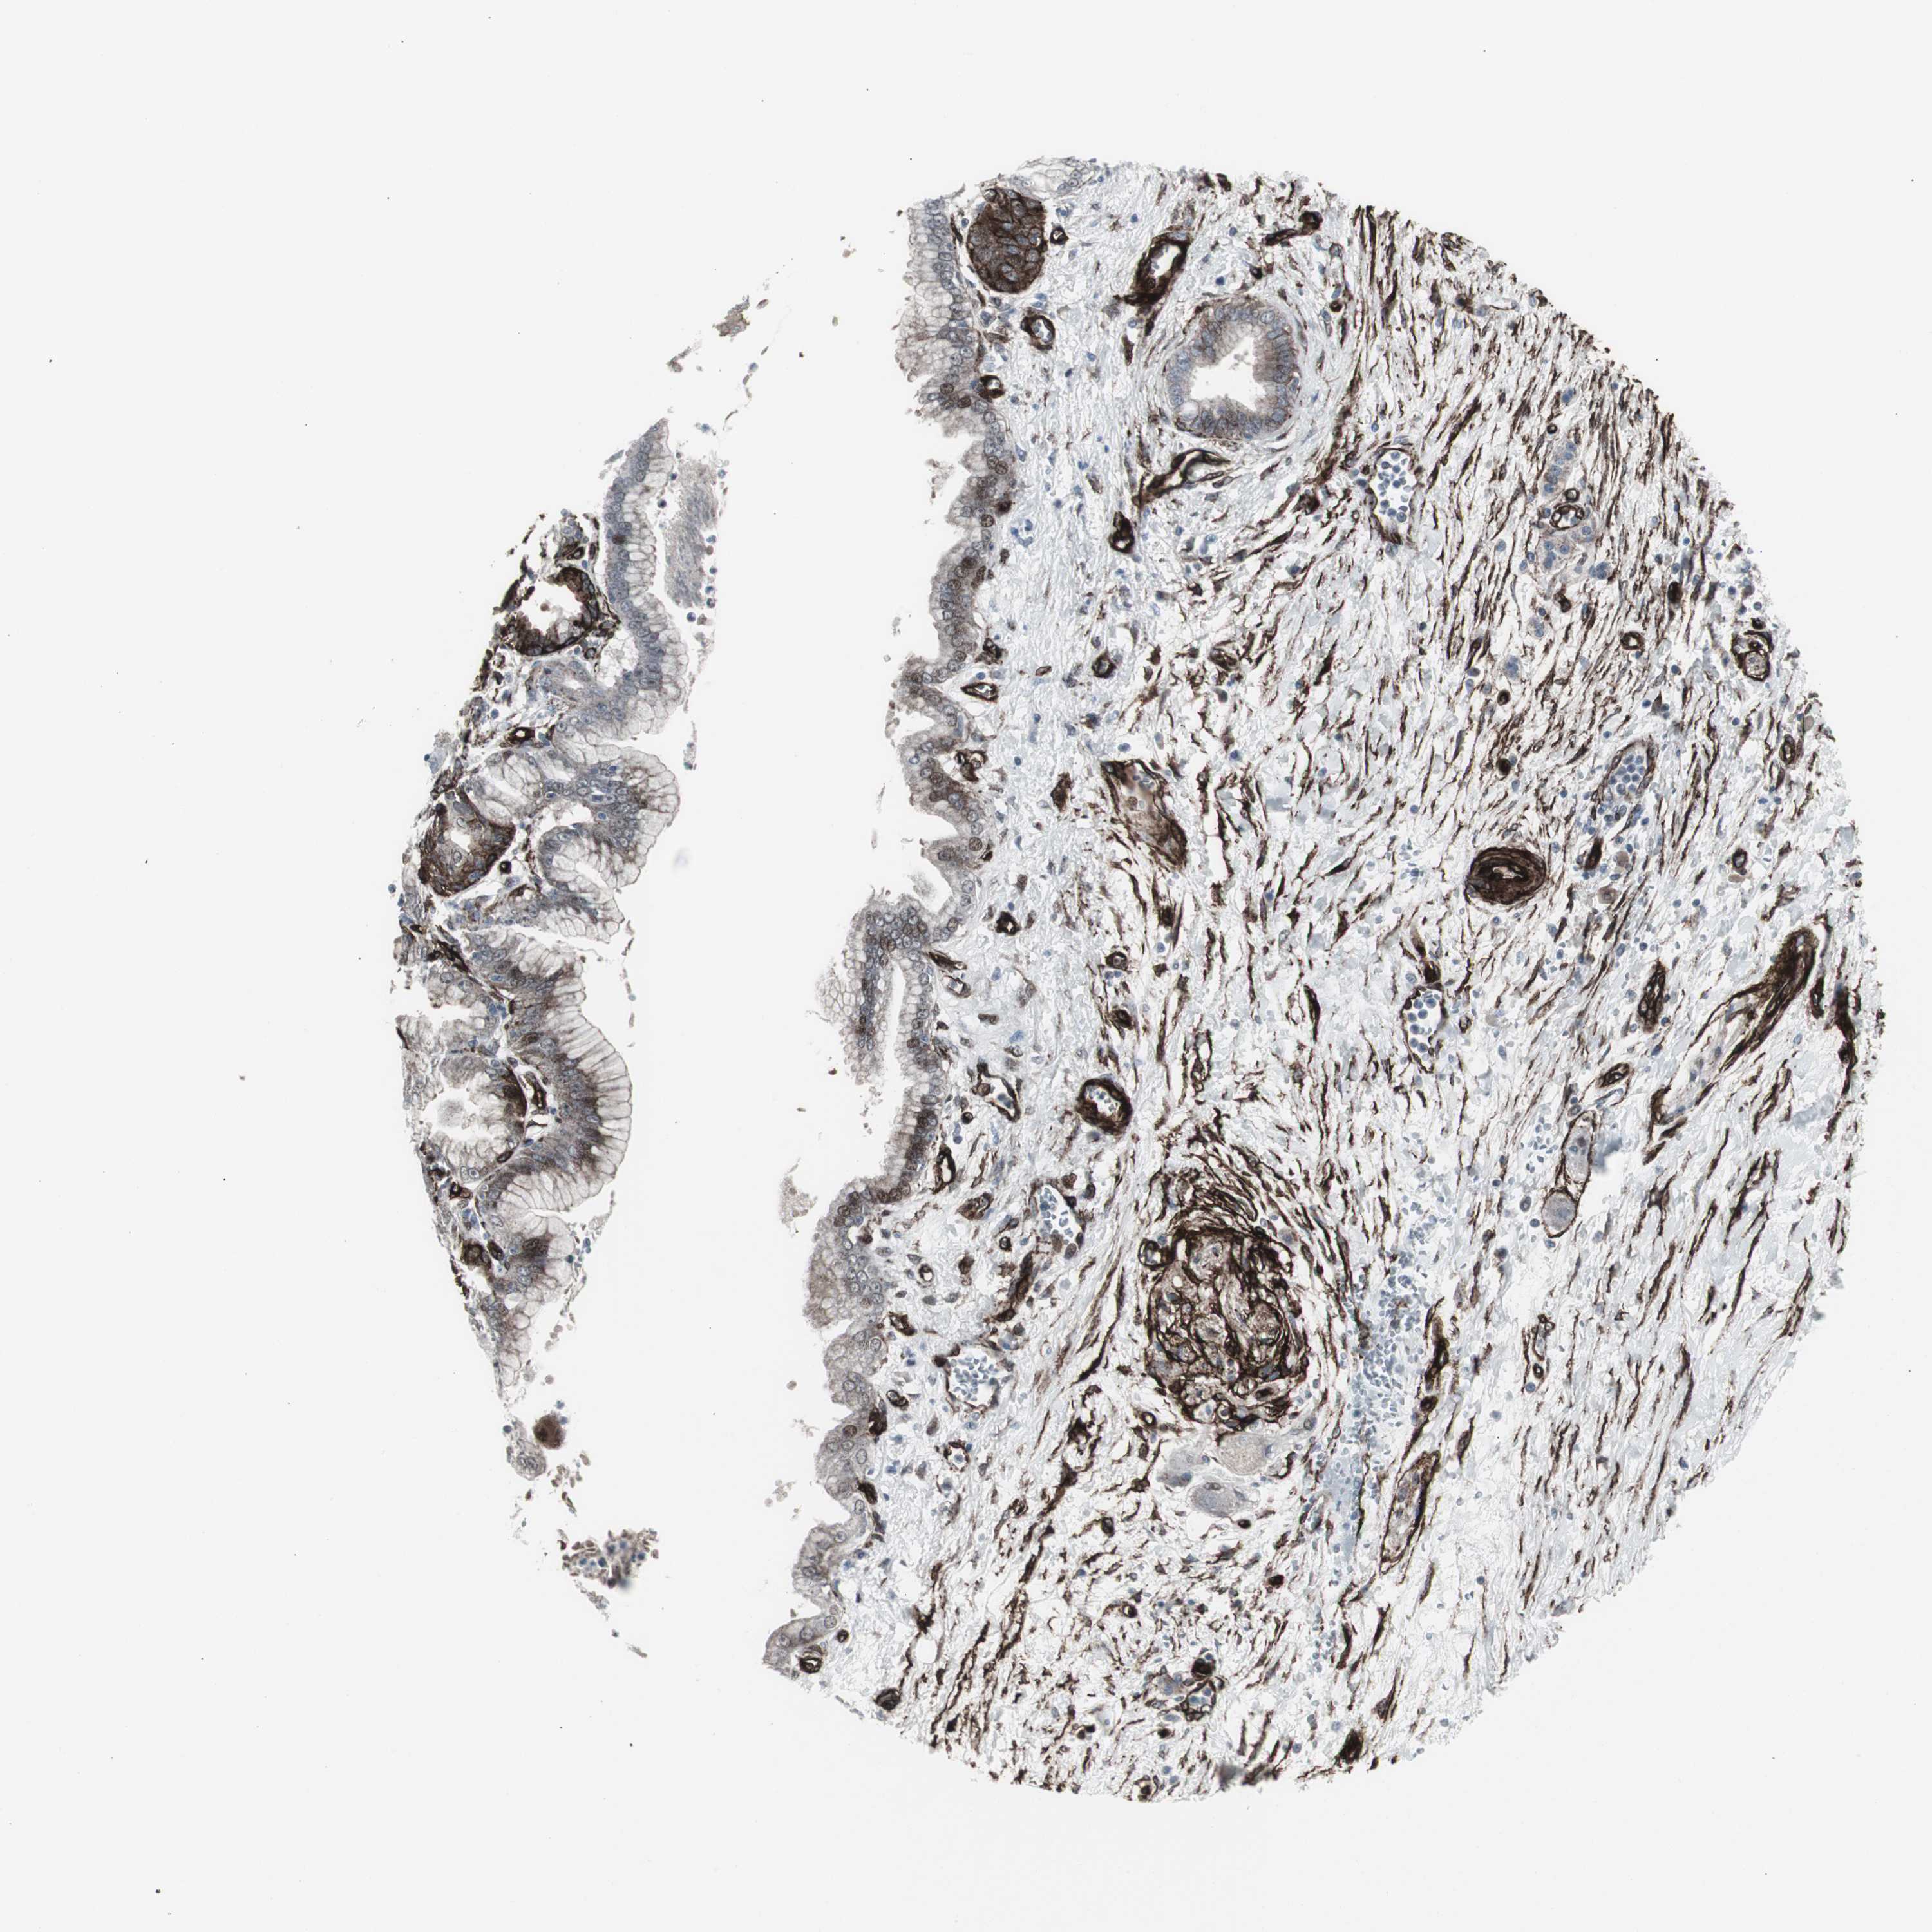

PANCREATIC CANCER - Protein expressioni

A mouse-over function shows sample information and annotation data. Click on an image to view it in a full screen mode. Samples can be filtered based on level of antibody staining by selecting one or several of the following categories: high, medium, low and not detected. The assay and annotation is described here.

Note that samples used for immunohistochemistry by the Human Protein Atlas do not correspond to samples in the TCGA dataset.

Antibody stainingi

Antibody staining in the annotated cell types in the current human tissue is reported as not detected, low, medium, or high, based on conventional immunohistochemistry profiling in selected tissues. This score is based on the combination of the staining intensity and fraction of stained cells.

Each image is clickable and will lead to virtual microscopy that enables deeper exploration of all samples and also displays staining intensity scores, fraction scores and subcellular localization as well as patient and tissue information for each sample.

Antibody CAB005579

Staining

High

Medium

Low

Not detected

Intensity

Strong

Moderate

Weak

Negative

Quantity

>75%

75%-25%

<25%

None

Location

Nuclear

Cytoplasmic/membranous

Cytoplasmic/membranous,nuclear

Adenocarcinoma, NOS

Adenocarcinoma, metastatic, NOS